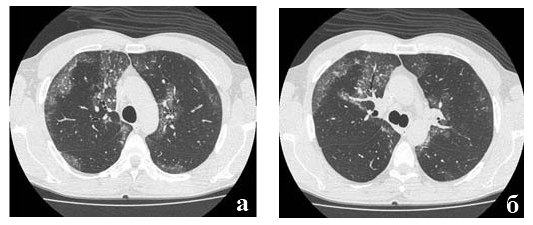

Рис. 3. Фрагмент компьютерной томограммы больного альвеолярным протеинозом.

Участки "матового стекла", отграниченные от неизмененных участков. Утолщение междольковых перегородок в зонах "матового стекла".

Подробнее следует остановиться на характерных симптомах альвеолярного протеиноза выявляемых при компьютерной томографии высоких разрешений (рис. 2, 3):

- Наличие зон «матового стекла»:

- всегда одновременно в обоих легких

- достаточно четко отграничены от неизмененной паренхимы, что придает им «географический вид», могут иметь очень четкие контуры в случае прилежания к плевре междолевых щелей

- нет четкой анатомической привязки

- процесс может быть фокальным («пятнистым») или распространенным.

- Утолщение междольковых перегородок:

- только в зонах «матового стекла»

- характерный вид «булыжной мостовой» ("crazy paving"). В основе симптома - утолщение междольковых перегородок, обусловленное отеком и неравномерной лимфоцитарномакрофагальной инфильтрацией [4].

При компьютерной томографии получена картина, позволившая заподозрить альвеолярный протеиноз (рис. 4).

Рис. 4. Фрагменты компьютерной томограммы больного Б.

Выявляются 2-сторонние зоны "матового стекла" с утолщением в них междольковых перегородок, четко отграниченные от интактной легочной паренхимы.

Рис. 10 а, б. Фрагменты компьютерной томограммы больного Б. после про ведения БАЛ.

Уменьшение распространенности и интенсивности зон "матового стекла).

По данным КТВР после проведения БАЛ также выявлена положительная динамика (рис. 10 а, б).